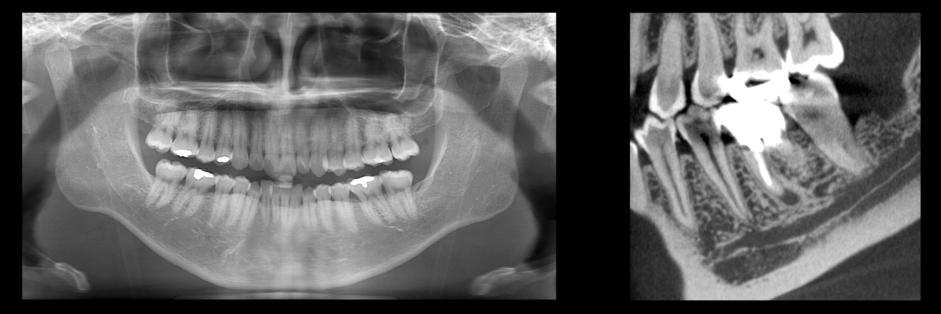

歯科専用エックス線撮影装置

- 顎関節や顎の骨を含め、左の奥歯から右の奥歯まで広い範囲を撮影できます。

- 歯科・口腔外科でよく用いられ、主に親知らずの抜歯や歯周病の診断、インプラント治療の際に撮影します。

「新規機器を導入しました」

2019年9月に歯科専用エックス線撮影装置を更新しました。

新たにコーンビームCT(CBCT)撮影が可能となりました。

この装置で撮影したCBCT画像は、歯科・口腔外科領域に特化した、より微細なもので、治療や手術に用いられます。

以前は歯科専用エック線装置とCT装置それぞれで撮影していたものが、

この装置一台で撮影できるため、患者様にお待ちいただく時間も短くなりました。